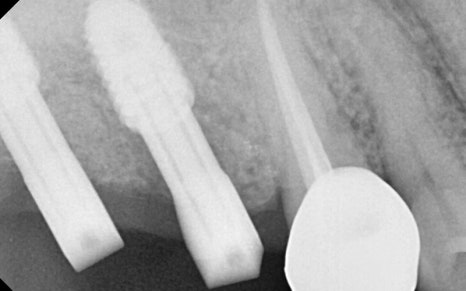

식립 후 한달체크때

별다른 이상이 없는것을 확인해주었고

임플란트가 잇몸뼈에 잘 유착될동안

기다려주기로 하였습니다.

✅ 2차 수술 완료

임플란트가 잇몸뼈에 잘 유착된것을 확인하고

2차 수술을 진행해주었고,

본뜨기 작업을 시행 후, (왼쪽 사진)

맞춤형 지대주를

체결해주답니다. (오른쪽 사진)